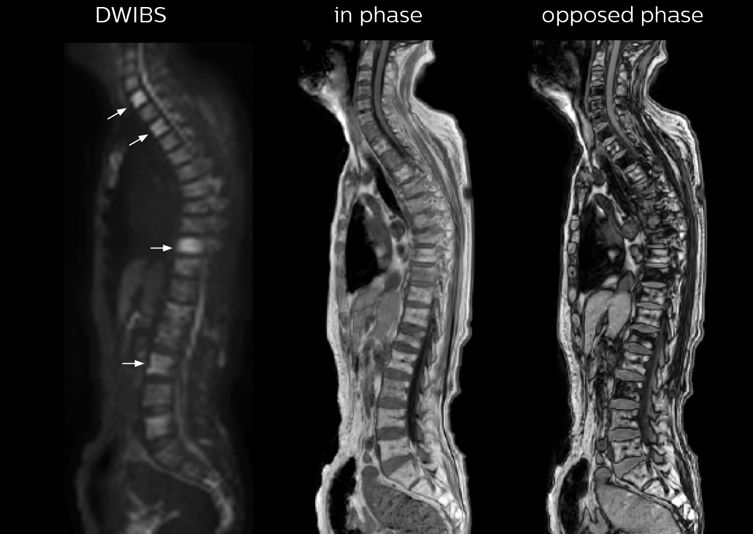

“In-phase and out-phase sagittal T1-weighted FFE images help us to visualize and further characterize bone lesions such as metastasis and bone-marrow hyperplasia that have high signal on DWI. These images are also used throughout radiotherapy, to monitor changes in the fatty bone marrow.”

“mDIXON FFE allows us to quickly get information we need to assess the presence of fat. That gives us more information when we need to diagnose bone lesions, and when we are asked to judge fat-containing lesions such as hepatocellular or renal carcinoma,” Dr. Nobusawa says.

“The mDIXON fat images can help us to differentiate fatty bone marrow from bone lesions. This is especially useful in elderly people, who tend to have fattier bone marrow. The water images provide a high signal-to-noise ratio in the intestinal canal, which is valuable for visualizing lesions in the colon,” he says.

Kawasaki Sawai Hospital’s whole body protocol also includes an mDIXON FFE sequence. Because mDIXON provides images for four contrast types – water only, fat only, in-phase and out-of-phase – from a single acquisition, it is useful in many ways.